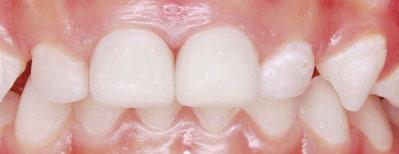

Several clinical solutions exist for primary anterior teeth with multisurface decay. Full coronal restoration of carious primary incisors may be indicated when caries is present on multiple surfaces, pulpal therapy is indicated, caries may be minor, but oral hygiene is very poor, or in a child with severe early childhood caries or a high caries risk diagnosis.1 Depending on the clinical scenario, a minimally invasive approach with the utilization of a high viscosity glass ionomer cement (HVGIC), with or without the combination of silver diamine fluoride (SDF) in a strip crown form, may pause the caries progression and provide an adequate clinical solution. Resin composite strip crowns have shown 80% retention rates and adequate parental satisfaction,1-4 although composite resin strip crowns have shown lower retention rates in teeth with decay involving three or more surfaces and particularly in children with a high caries risk4-6 (Figure 1). This could be from the continued high caries risk behaviors of the patient, as composite resin strip crowns in this population have shown to have increased inflamed marginal gingiva and gingival bleeding, increased plaque retention along the restoration, and loss of some restorative material.5,6

Alternatively, a resin-faced stainless steel crown provides a full coverage restoration with excellent retention.7 These crowns can serve as a full-coverage restoration with or without the resin facing, but the loss of resin facing can be a major esthetic concern for parents.7 Preformed pediatric zirconia crowns address many of the undesirable clinical outcomes of other restorative materials. Their biocompatibility, demonstration of excellent marginal gingival health, low plaque retention, high parental esthetic acceptance, and high survival probabilities make them an excellent clinical choice in the patient with severe early childhood caries.1,4,5,8-13

With parental interest increasing in esthetic treatment options for complex anterior caries, preformed pediatric zirconia crowns are becoming the treatment of choice for patients with a high caries risk or a severe early childhood caries diagnosis.14

This review discusses three clinical cases in which NuSmile® ZR (NuSmile, Houston, Texas) anterior pediatric zirconia crowns were the correct clinical decision in varying clinical scenarios.